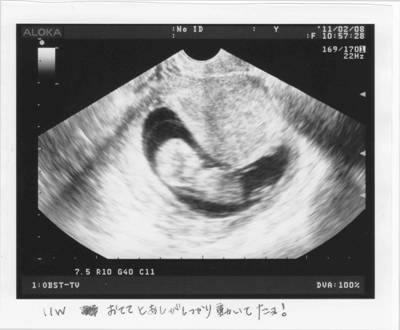

健診。

過去の経緯と出血から、今日も初診担当の教授が時間を掛けて見て下さった。

これほど時間をかけた内診は初めてだとおママ。安心である。

順調に育っている。

血腫が小さくなっているので、先週の出血はこの血腫の一部であろう。

とのこと。よって再び同様な少量の出血が見られるかもしれないとのことである。

先週指摘されたN T浮腫については、大きくなっていないことが確認でき、こちらも問題ないとのこと。

夜、エコー写真を見る。

Sの11Wと比べて遜色ない。

アゴが映っているので横顔らしい。

ちょうど目のようなものも映っているが、これはたまたまできた影だろうとの事。